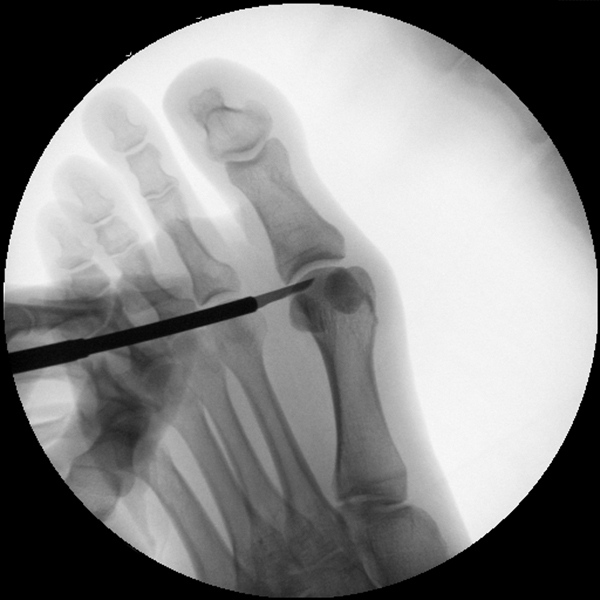

Der von Isham/Reverdin beschriebenen minimal invasiven Technik zur Korrektur einer Hallux valgus Deformität liegen 4 Operationsschritte zu Grunde:

1. Abtragung der Exostose am Köpfchen des 1. Mittelfußknochens

2. Subcapitale intraartikuläre Osteotomie

3. Laterales Release

4. Akin Osteotomie der Großzehengrundphalanx

Die Folge der Operationsschritte sollte strikt von 1. - 4. erfolgen, da ansonsten die mediale Closing Wedge Osteotomie bei vorzeitigem lateralem Release und/oder Akin Osteotomie nicht geschlossen werden kann. Nach der von Isham beschriebenen Originaltechnik finden Implantate keine Anwendung, zur Sicherung und besseren Fixation können osteosynthetische Verfahren angewandt werden (siehe auch Fehler, Gefahren und Komplikationen).